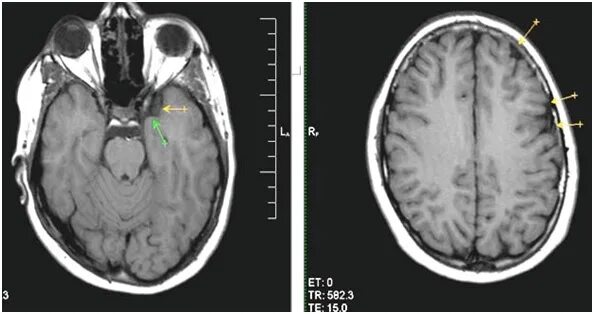

Расширение ликворосодержащих пространств